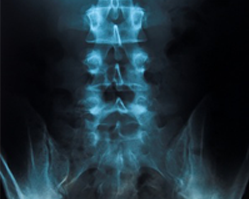

إزالة ضغط القرص الفقري بالليزر عبر الجلد (PLDD) هو إجراء طبي يستخدم أشعة الليزر لعلاج الألم الناتج عن فتق القرص الفقري في الظهر والرقبة. على مدار القرن الماضي، تم إجراء استئصال الصفيحة الفقرية واستئصال القرص الفقري بالتدخل الجراحي التقليدي، ولكن منذ ذلك الحين، تطورت التكنولوجيا وتطورت أساليب التدخل الجراحي الأقل توغلًا.

إزالة ضغط القرص الفقري بالليزر عبر الجلد (PLDD) هي أول عملية من نوعها، طُوّرت في أوائل الثمانينيات. مع مرور الوقت، تم تحسين هذه العملية بإدخال ليف بصري في القرص الفقري بتوجيه الأشعة السينية. يُقلّص الليزر الجزء الصغير من المادة الداخلية للقرص، والذي يُسمى النواة اللبية. ومنذ ذلك الحين، أُجريت آلاف عمليات إزالة ضغط القرص الفقري بالليزر عبر الجلد بنجاح حول العالم.

علاج إزالة ضغط القرص بالليزر عبر الجلد لفتوق الأقراص العنقية والظهرية (باستثناء T1-T5) والقطنية (يجب عدم الخلط بينه وبين علاجات الليزر الأخرى) هو تقنية جديدة غير جراحية تُجرى تحت التخدير الموضعي في إيطاليا. يُسلط شعاع ليزر على النواة اللبية للفقرات المعنية بعد إدخال ليف بصري؛ ويُوضع هذا الليف على اتصال بالنواة اللبية من خلال إبرة تُوضع في ظهر المريض، ويتم ذلك تحت مراقبة الأشعة السينية. من الناحية الفيزيائية، يُنتج PLDD تبخيرًا لجزء على الأقل من النواة اللبية، ويُحدد تخفيف الضغط على العصب المتأثر (لا يهدف هذا الإجراء إلى تقليل الفتق أو إخفائه، بل إلى تقليل الضغط على العصب بشكل ملحوظ).

- بين الفقرات توجد أقراص تُشكّل حلقة وصل. يتكون كل قرص بنسبة ٧٥٪ من الماء، وهو مُحاط بكبسولة.

- يمكن أن تؤدي الإصابة أو التآكل إلى إضعاف الكبسولة؛ ونتيجة للضغط من الفقرات، يتم دفع جزء من محتويات القرص إلى الخارج، مما يشكل فتقًا، والذي بدوره يضغط على أعصاب الظهر والساقين، مما يسبب آلامًا شديدة.